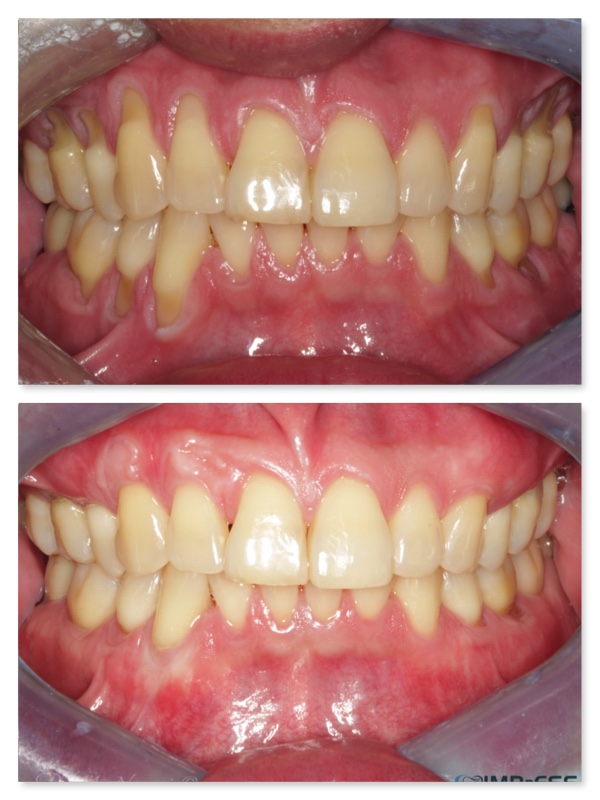

Connective Tissue Gingival Grafting for Gingival Recession